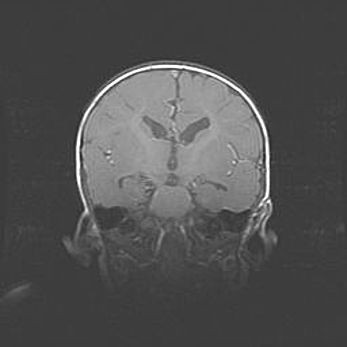

Открытая гидроцефалия.

Возраст: 6 месяцев 15 дней

Вес: 6200 г

Пол: женский

Окружность головы: 41 см

Срок гестации: 38 недель

Гидроцефалия головного мозга у новорожденных – это скопление избыточного количества цереброспинальной жидкости в головном мозге. Ее избыточное скопление в мозге приводит к патологическому расширению желудочков мозга (четырех полостей, расположенных в глубине белого вещества мозга, заполненных цереброспинальной жидкостью и связанных узкими проходами).

Открытый тип гидроцефалии (сообщающаяся) наблюдается тогда, когда нарушен механизм всасывания ликвора в системный кровоток. При этом типе причиной заболевания чаще всего является перенесенные ранее инфекции (например: менингит),  либо же наличие крови в субарахноидальном пространстве.